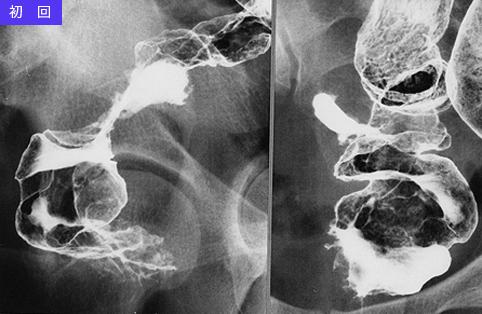

症例提示(所在地,施設名等): 東京都・ 国立がんセンター中央病院と九州がんセンターの共同作成

疾患(病理主体)の分類悪性リンパ系腫瘍/悪性リンパ腫

部位(臓器別)大腸/直腸

検査方法X-P

病変の最大径(ミリ)40以上